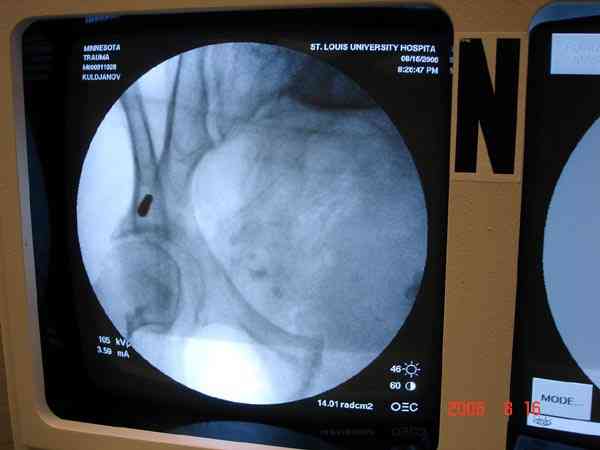

Примерно такой фиксатор наложил вчера ночью, но патология была экстренная травма: больному 53 года, поступил после мотоциклетной травмы, черепно-мозговой, абдоминальной, челюстно лицевой с потерей одного глаза, сосудистой и из скелета перелом крестца слева с диастазом симфиза и множественные переломы ребер.

Здесь соблюдался алгоритм больному с внутритазовым кроветечением после нестабильного перелома таза.

Для стабилизации перелома и кровопотери, сперва была попытка наложения простыни вокруг таза для уменшения объема таза. Для оперативного доступа в области живота и передней части таза простыню заменили на Beam Bag (матрац который после удалении воздуха принимает контуры тела).

Одновременно с хирургами, которые занялись ксплоративной лапаротомией, мы приступили к фиксации временным аппаратом для уменьшения диастаза симфиза. После установки аппарата удалось стабилизировать давление, потом наше место занял сосудистый хирург, который нашел кровоточащую левую артерию epigastrica. Кровоточаший сосуд затромбизировал эндоваскулярно введением 4 coil placement.

Много кровепотери было из лицевых ран. Кроме забрюшинной гематомы, крови накопилось в абдоминальной части между мышечными стенками и под кожей. Кровопотерю заместили более 20 доз препаратов крови и INR опустился изначалнего 9.5 до 1.0 в конце. Находится в реанимации, стабильный, надеемся через несколько дней займемся окончательной фиксацией переломов костей таза.